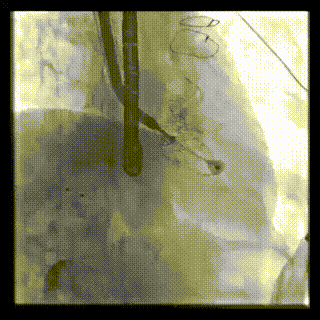

本周三例接受LuX-Valve Plus經(jīng)血管三尖瓣置換術(shù)的患者中,第一例患者為冠狀動(dòng)脈旁路移植術(shù)+Bentall+二尖瓣成形術(shù)后;第二例患者為永久起搏器植入術(shù)后,存在跨三尖瓣導(dǎo)線;第三例患者合并房顫、房缺及左心耳封堵術(shù)后。

三例患者入院后,葛均波院士團(tuán)隊(duì)周達(dá)新教授、潘文志教授、張?jiān)床┦?、陳莎莎博士及心超室的潘翠珍教授、李偉教授?duì)患者的情況進(jìn)行詳細(xì)評(píng)估和討論,最終決定為三例患者選擇LuX-Valve Plus40mm、50mm和50mm型號(hào)的瓣膜進(jìn)行手術(shù)治療。手術(shù)后即刻拔除氣管插管,術(shù)后患者三尖瓣反流癥狀得到顯著改善,復(fù)查心超結(jié)果顯示人工三尖瓣瓣膜支架固定穩(wěn)定,瓣葉關(guān)閉形態(tài)未見異常,未見明顯反流。